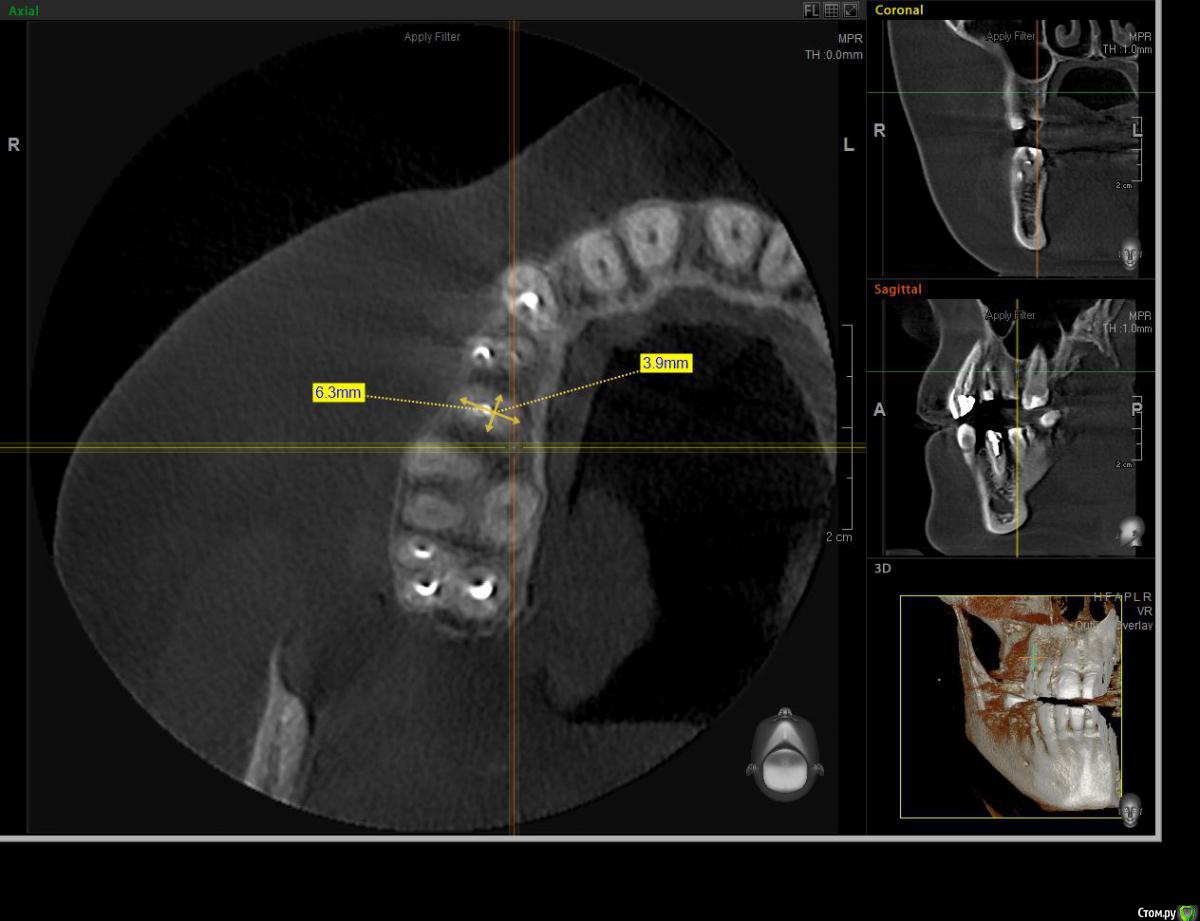

AlexanderGudkov Опубликовано 5 июля, 2017 Автор Поделиться Опубликовано 5 июля, 2017 Александр, формик 8.5 не нашёлся чтоль?))При этой позиции импланта для 8,5 пришлось бы море кости спилить))Так - то я широкие фдм люблю))http://s014.radikal.ru/i328/1707/ba/95cd7072120e.pnghttp://s019.radikal.ru/i603/1707/12/0f67ce0cd861.png Ссылка на комментарий